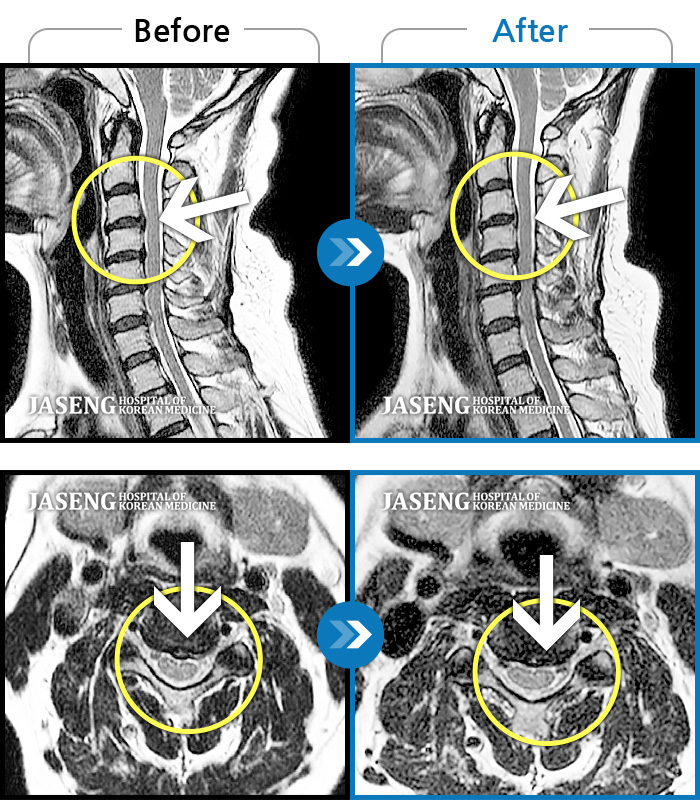

목디스크

많이 본 사례

강남 · 강만호 원장

좌측 목 통증과 좌측 팔저림이 심해서 업무가 힘들었습니다.

촬영시기

2023.07.19 ~ 2024.07.20

2024.07.25